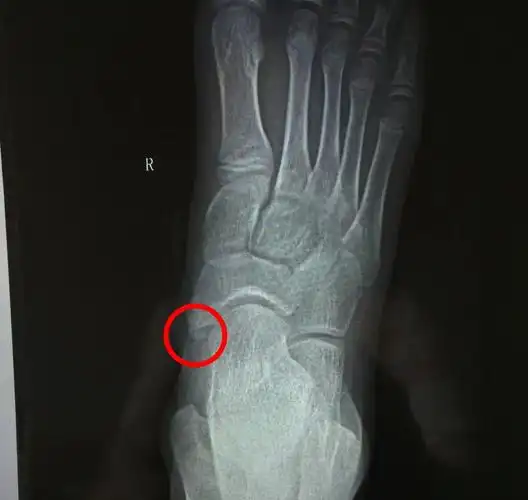

儿童足部副舟骨的治疗_先天性足畸形_先天性足畸形治疗方式 - 好大夫